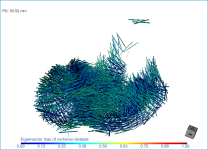

Screen capture of the completed tutorial

Below are some examples of vector field-based anisotropy maps shown from different aspects. The top row includes visualizations of anisotropy magnitude, while the bottom row shows vector fields colored by orientation. The pair of images on the right show maps that are clipped.

The 3D vector field-based anisotropy map appears in the 3D view at the default settings, with the vectors corresponding to the highest surface anisotropy colored yellow and those corresponding to the lowest, or isotropy, colored blue.

NOTE The Jet LUT is often a good color scheme choice. In this LUT, vectors corresponding to the highest surface anisotropy are colored red, while those corresponding to the lowest, or are isotropic, are colored blue.

- Threshold the vector field-based map to show only high or low anisotropy areas with the Range slider, as shown below.

The thresholded map shown below shows only low anisotropy areas located near articulating surfaces.